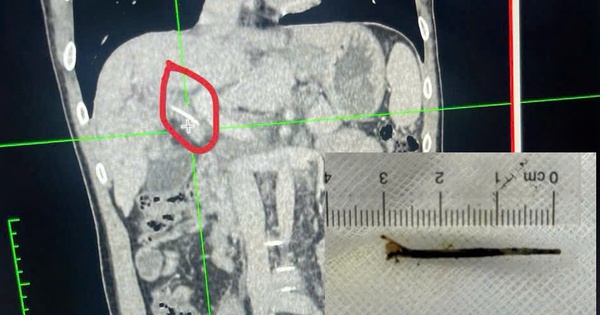

Bệnh nhân 45 tuổi bị đau bụng hạ sườn phải kéo dài, kèm vàng da, vàng mắt, nghi ngờ bị ung thư… vào viện bất ngờ phát hiện bị hóc xương cá dài 3 cm xuyên qua thành dạ dày vào đường mật.